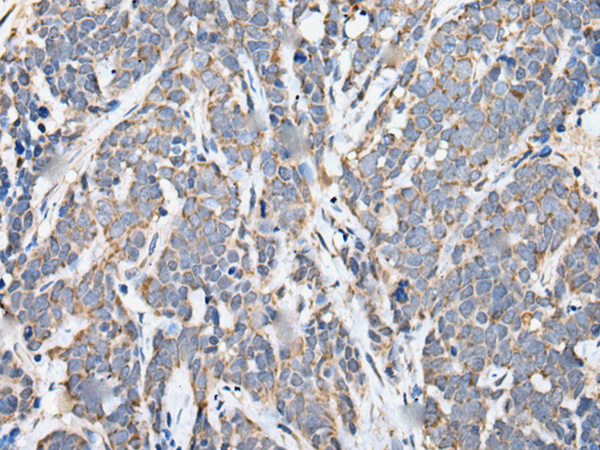

分类: 科研抗体货号: P05706别名: MT2; FGQTL2; MEL-1B-R应用: IHC反应种属: Human